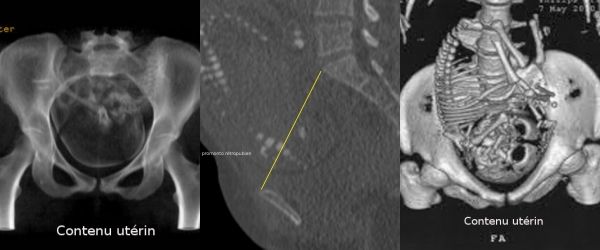

Les coupes sont également travaillées en mode rendu volumique. Il est ainsi possible d'obtenir très facilement les images pour l'étude morphologique du bassin.

Le foetus peut être facilement « effacé » afin de ne pas gêner l'étude anatomique du bassin maternel Il est aussi possible de mesurer les différents diamètres utiles sur ces reconstructions volumiques.

Grâce aux reconstructions en rendu volumique, il est possible d'apprécier ainsi facilement la morphologie du bassin, en particulier du détroit supérieur.

Ces reconstructions sont de plus tout à fait lisibles et compréhensibles par des obstétriciens ou des sage-femmes.